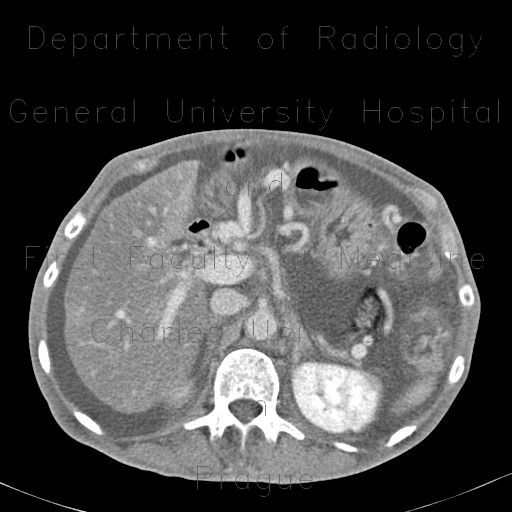

CT shows marked enhancement of the inner layer of colonic wall, edema of bowel wall - both small and large bowel, massive dilatation and tortuosity of mesenteric veins with shunting due to occlusion of superior mesenteric vein. Note also the presence of ascites and decreased density of liver parenchyma due to steatosis.